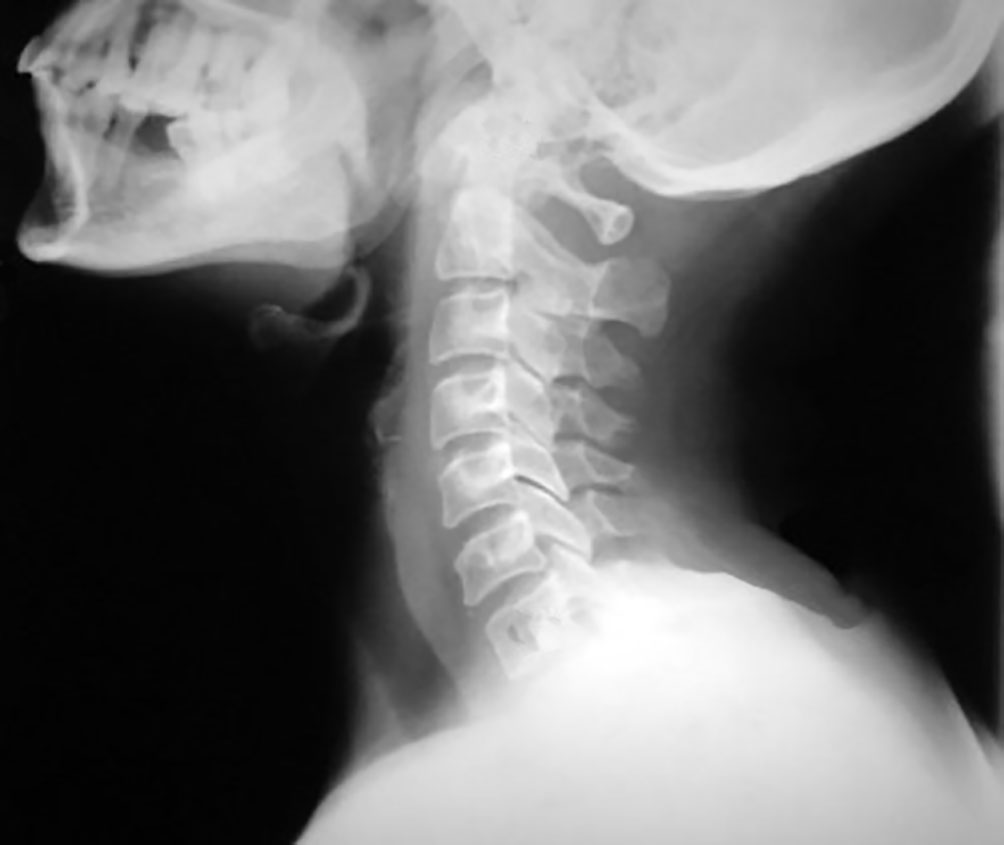

Cuando duele el cuello se lo siente rígido, es porque están afectados los músculos, los nervios, las vértebras o los discos intervertebrales. Es posible que en esas circunstancia se sienta dificultad en moverlo, especialmente cuando se lo gira de un lado hacia el otro y, si están comprometidos los nervios del cuello, se puede sentir también entumecimiento, hormigueo o debilidad en el brazo, en la mano o en la zona de la espalda. La causa más común del dolor cervical es la tensión o la distensión muscular (estiramiento violento de los tejidos), causados comúnmente por algunas actividades que estemos realizando.

Las caídas o accidentes pueden causar lesiones cervicales graves, como fracturas de las vértebras, latigazo cervical, lesión de los vasos sanguíneos e inclusive parálisis. En estos casos es primordial inmovilizar y evacuar al herido al centro asistencial más cercano. Por ello es esencial que cuando elijamos un lugar agreste demos aviso de nuestro itinerario tanto a las autoridades más cercanas como a nuestros conocidos.